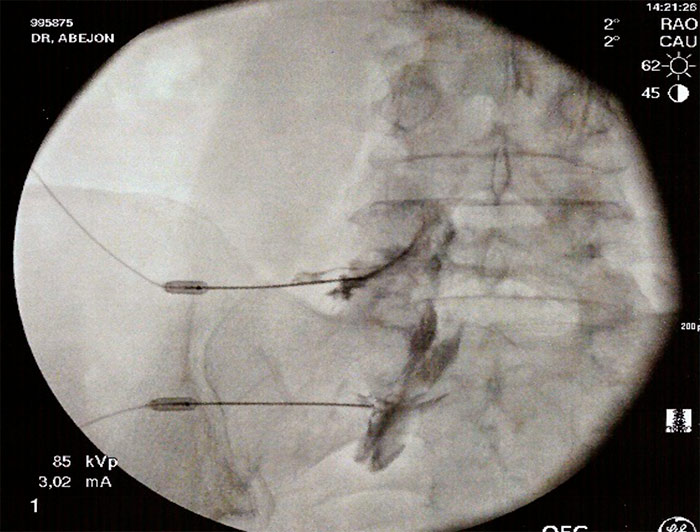

TÉCNICA

Con el paciente en decúbito prono, con almohada en el abdomen para corregir la lordosis fisiológica, se coloca el arco de fluoroscopia en en posición AP para localizar el espacio a tratar y se moviliza craneocaudalmente para eliminar el doble contorno. Una vez corregido el doble contorno se coloca el arco de rayos en posición oblicua ipsilateral (20-30º) hacia el lado afecto hasta localizar la imagen del  “perrito escocés”, y con un marcador radiopaco se localiza el target, que se encuentra en la unión de la cabeza con el cuello del perrito (6 horas de la aguja del reloj), se pinta con antiséptico la zona y se infiltra con anestésico local la dermis, tejido celular subcutáneo y planos musculares, insertándose la aguja (espinal 22G) en visión túnel. Se recoloca el arco de fluoroscopia en en posición lateral y se va avanzando la aguja hasta el extremo interno del foramen, momento en el que se administra contraste radiopaco a tiempo real, debiendo difundir al espacio epidural anterior. Se comprueba con el arco de fluoroscopia en en posición AP la difusión del contraste y se procede a la administración de la medicación (anestésico local y corticoide) que se realiza con mínima resistencia, y se finaliza con la retirada de la aguja con el mandril y la colocación de un apósito estéril.